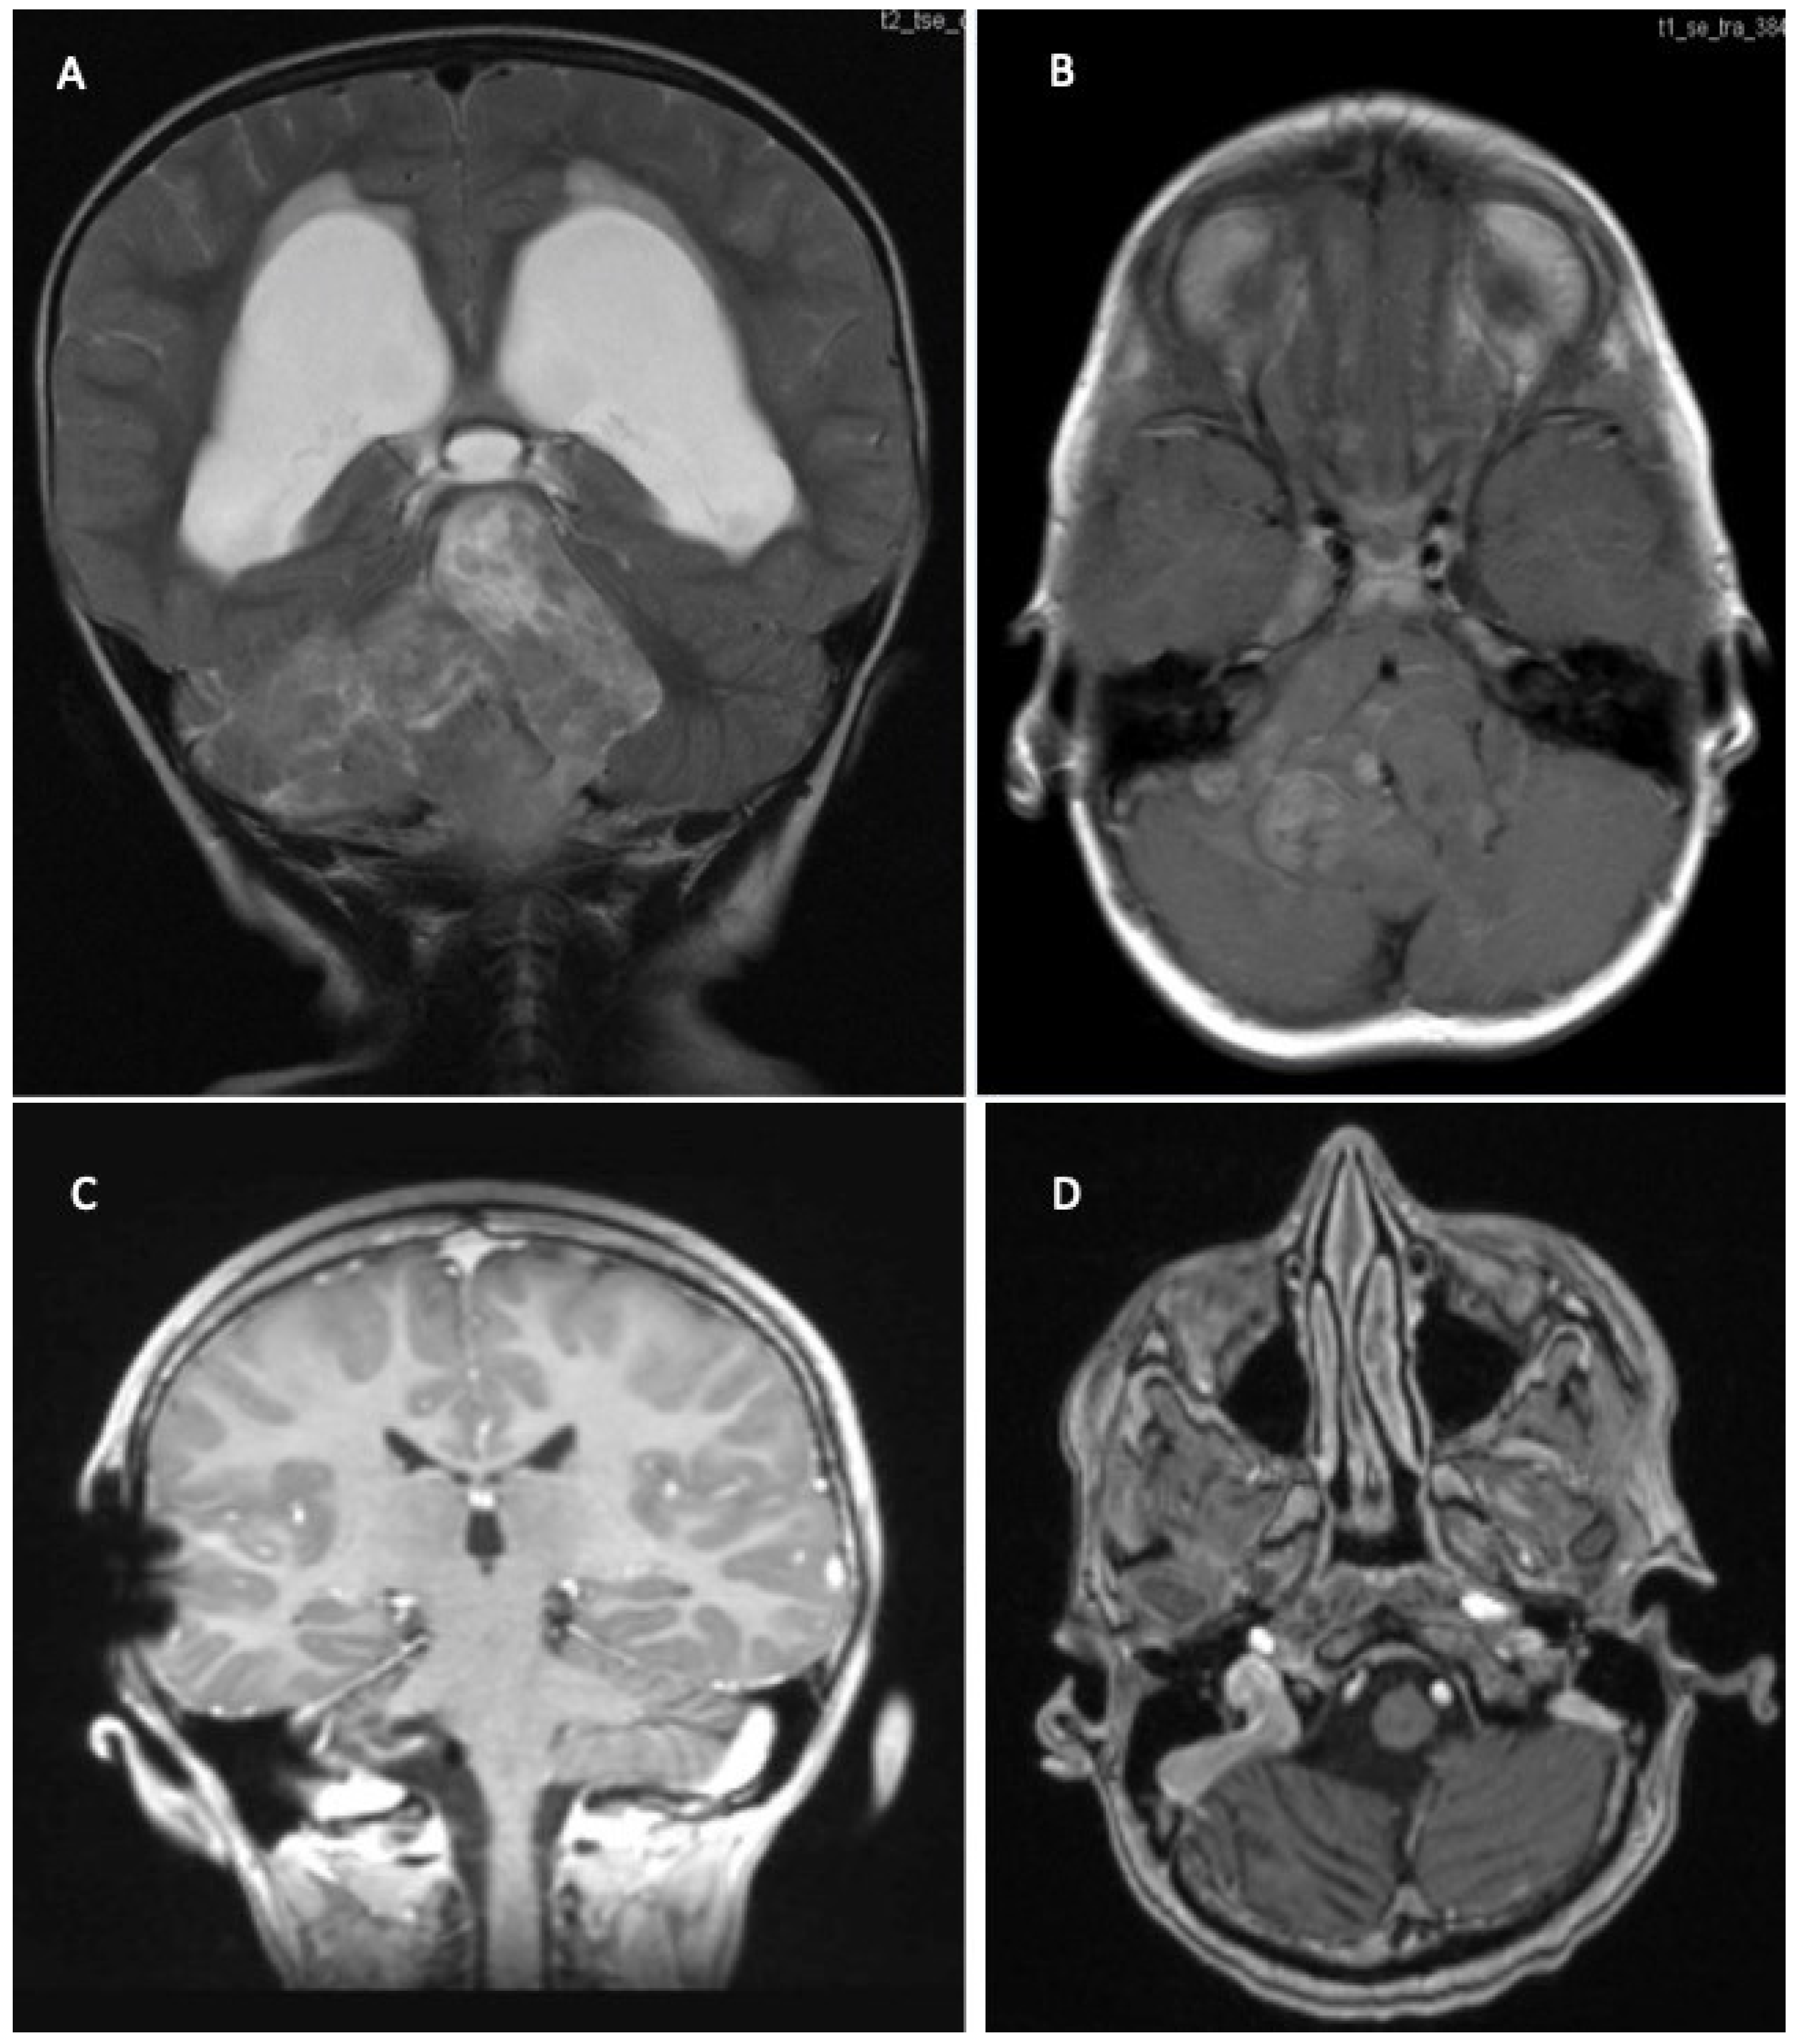

2. Clinical Assessment/Symptoms

3. Diagnostics

5.4. Ependymoma